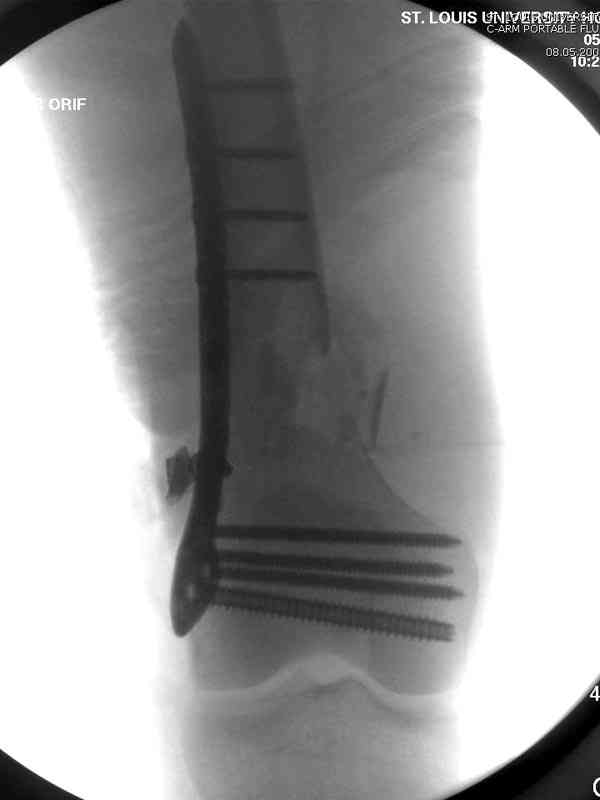

Вчера утром поступил больной с огнестрельной раной, осмотрен сосудистым специалистом, сделана ангиограмма (снимки) Во время операции при вскрытии обнаружили кровотечение, рану забили салфетками, установили пластину locking DePuy.

Из-за возрастающего давления в компартменте сделана фасциотомия и вызванный сосудистый хирург ушил разрыв вены на уровне перелома. Все раны оставлены открытими, в пятницу закроем.